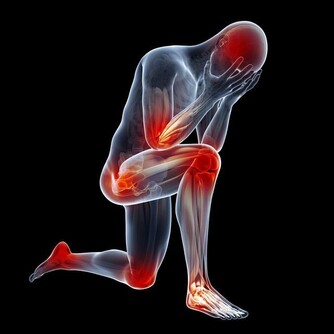

六、軀體疾病引起的繼發性抑鬱症如心髒病、肺部疾病、內分泌代謝疾病甚至重感冒、高熱等,都可引發這類抑鬱症。

6.疲勞或者無精打采,幾乎每天都如此。